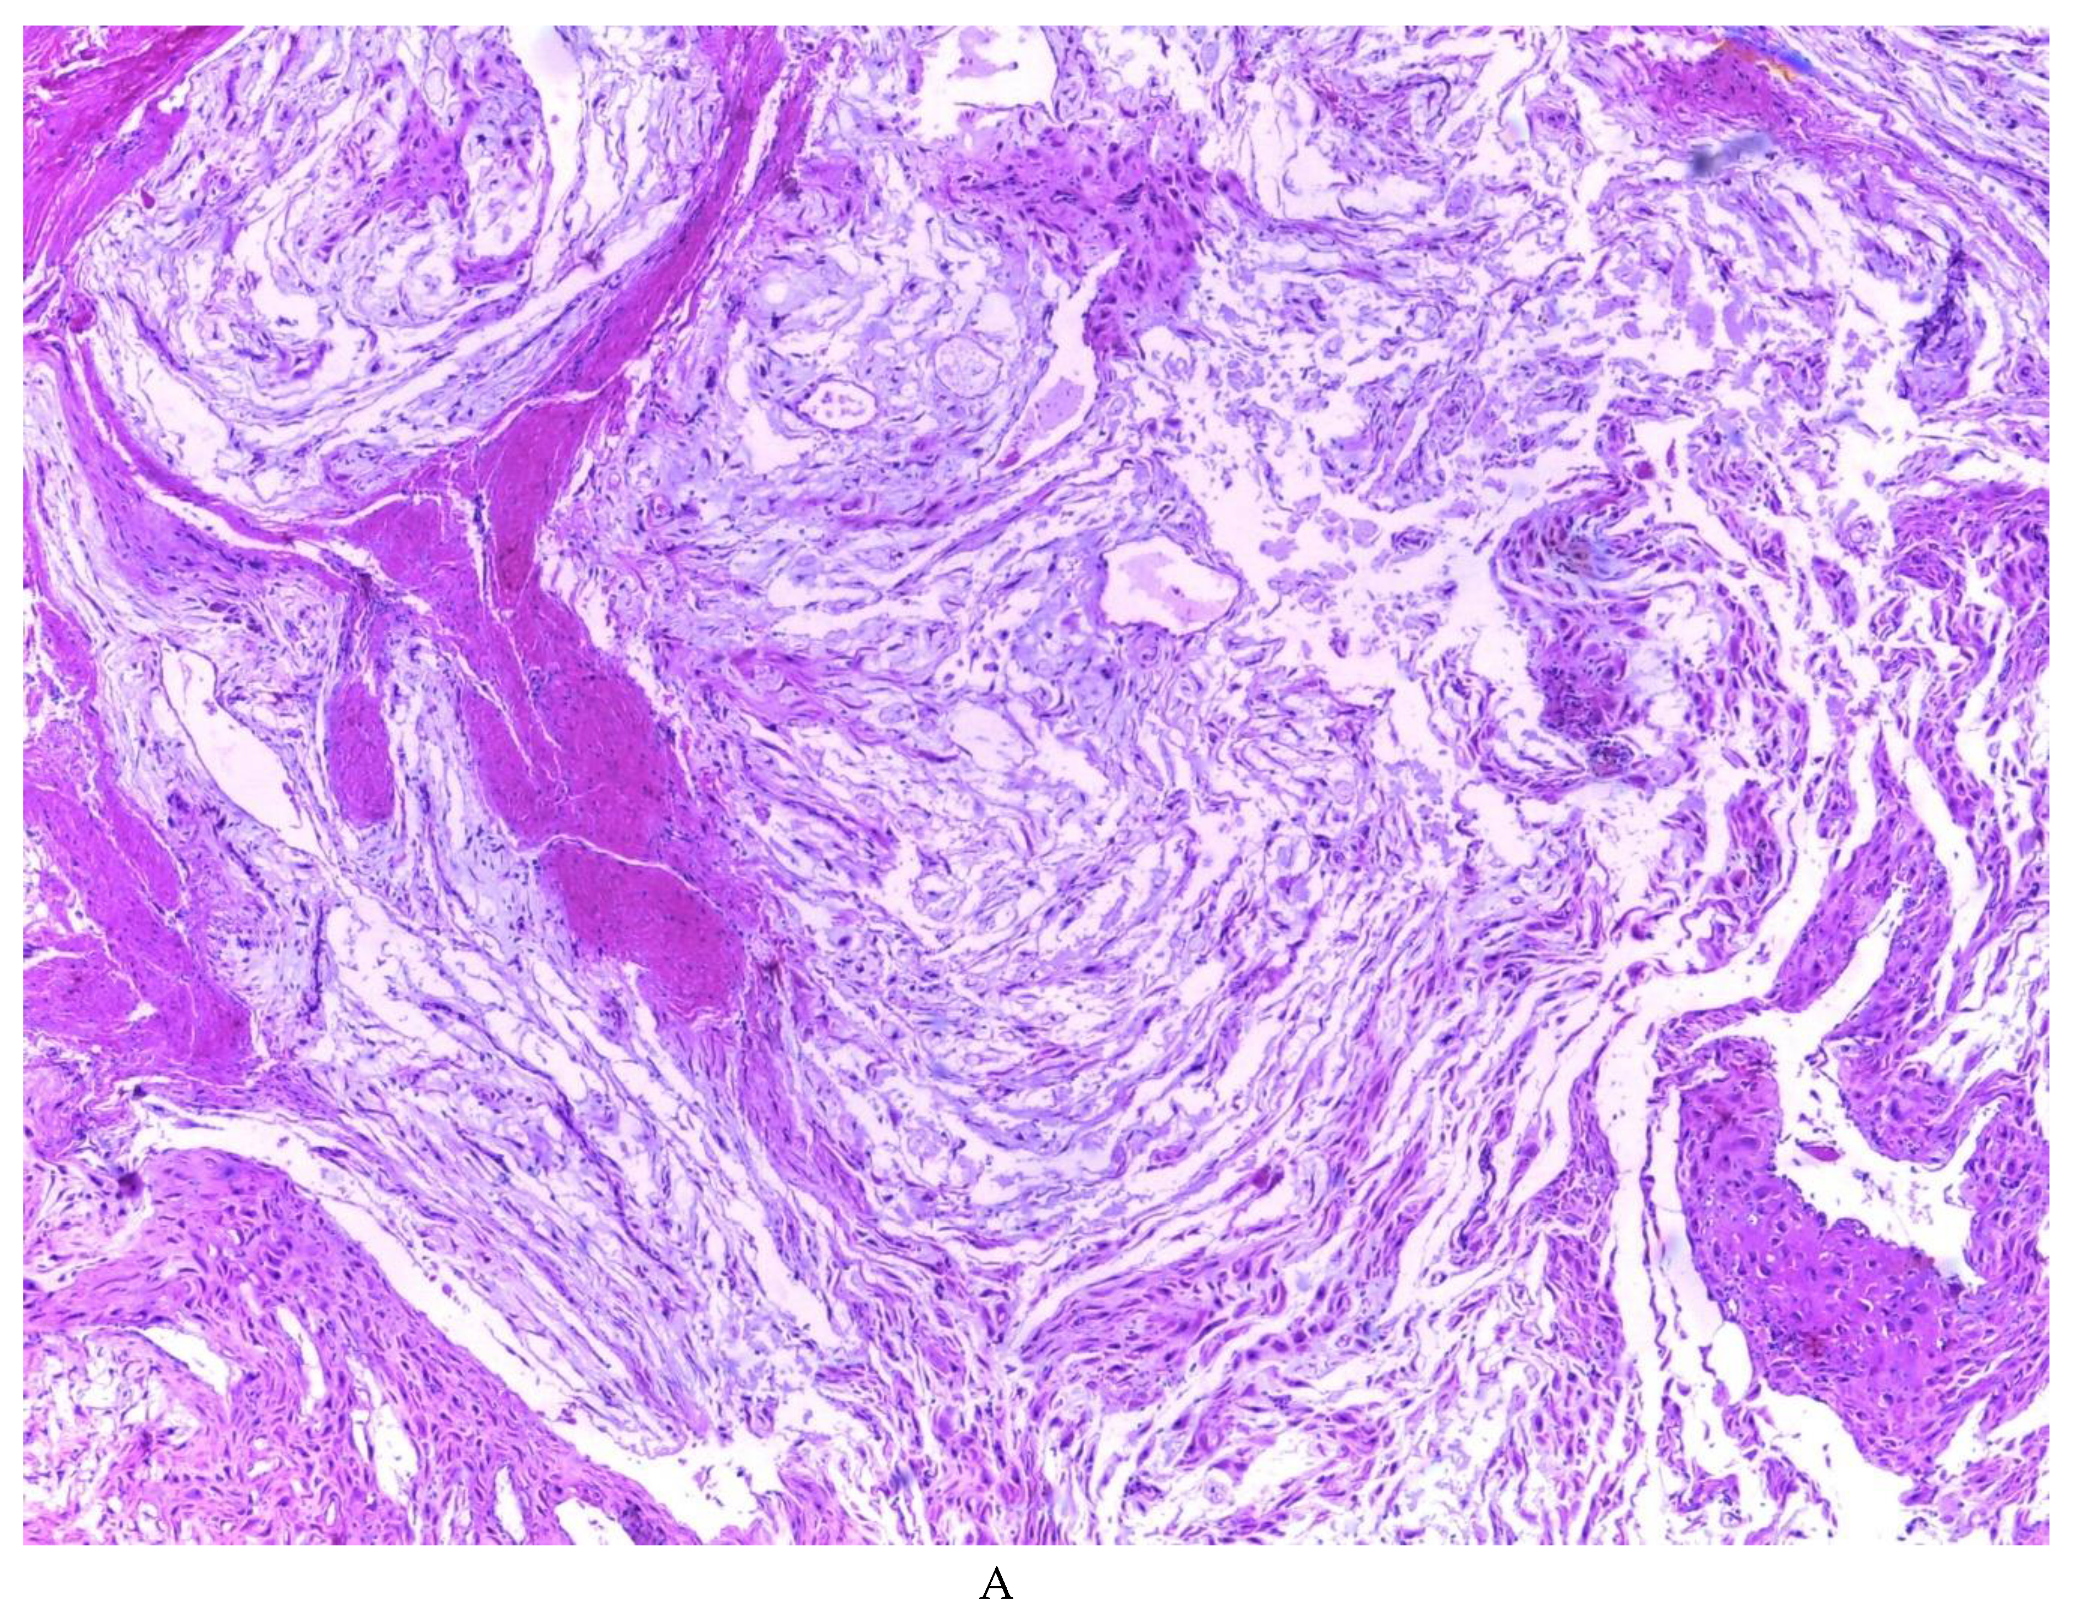

776 cases of endometriosis were collected between the two institutions participating in the study, in different anatomical sites (Table 1, Figure 1), in which 54 of them presented a myxoid stroma greater than 50% with respect to the cellularity of the samples. and that represent 6.95% of the total endometriosis examined with the following locations: omentum (4/20), ileum (2/4), ovary (14/216), parametria (2/9), soft tissues (28/235), salpingus (3/77), bladder (1/4). The clinical records of these patients were consulted and the common denominator was that the women were in the surgical (41/57) or physiological (7/39) puerperium in a period of time from 24 hours postpartum to six months after said event. Macroscopically, two different lesions were observed: the first one, which is the most frequent, presents as a non-encapsulated lesion with pushing edges of a fibromyxoid appearance; the second and less frequent, a well-defined lesion, partially or totally encapsulated, the cut surface is shiny, gelatinous in appearance, multilobed, light brown to brown in color with focal areas of recent and old hemorrhage, these lobes are separated by fibrous septa (Figure 2). Histologically, it was found in all the samples evaluated at least 50% of myxoid stroma with some fine connective tissue septa with proliferation of stromal cells (Figure 3A), which present four variants in their shape: (1) Epithelioid stromal cells of wide eosinophilic cytoplasm with round nucleus with small nucleolus (Figure 3B), (2) Pseudolipoblast-type stromal cells with moderate cytoplasm, multivacuolated in their cytoplasm that can present eosinophils or be clear cytoplasm, with central nuclei of granular chromatin (Figure 3C), (3) “pseudosignet ring” stromal cells with nucleus and cytoplasm rejected to the periphery giving the aforementioned appearance (Figure 3D) and (4) immersed spindle cells with small nucleus and barely visible nucleolus (Figure 3E); Among these cells, the epithelial component is observed, which is forming tubules that vary in diameter, ranging from small tubules and large cystic dilations of the gland that presents a layer of low cubic to cylindrical epithelium, generally with an atrophic appearance (Figure 3F). Hyaline globules were found in the glandular lumens (Figure 3G). The extracellular matrix showed a composition by glusocaminoglycans evidenced in 100% of the cases by staining present for AA (Figure 4A–C), but without staining for PAS; however, the latter stained on proteinaceous globular material in the lumen of the endometrial glands (Figure 4D). Immunohistochemistry for CD10 was positive in 100% of the stromal cells with a mild to moderate reaction in the cytoplasm and membrane with a decidual appearance (Figure 5A,B). The ER and PR showed nuclear expression in 100% of the cases, with greater intensity in the ER (Figure 5C) than in the RP (Figure 5D); both hormone receptors were expressed on endometrial epithelial cells as well as on stromal cells. The cases of myxoid endometriosis examined did not present cytological atypia suggesting any precursor lesion of epithelial or stromal origin.

Figure 3. Histologic features of myxoid endometriosis: A) Myxoid stroma in 50% or more of the tissue, with proliferation of stromal cells. Identified stromal cell variants: B) epithelioid cells, C) lipoblast-like cells, D) signet-ring-like cells, E) spindle cells. F, G, H) Epithelial component formed by glands of variable size, with simple cuboidal to columnar epithelium with a non-atypical atrophic appearance, occasionally accompanied by luminal hyaline globules.